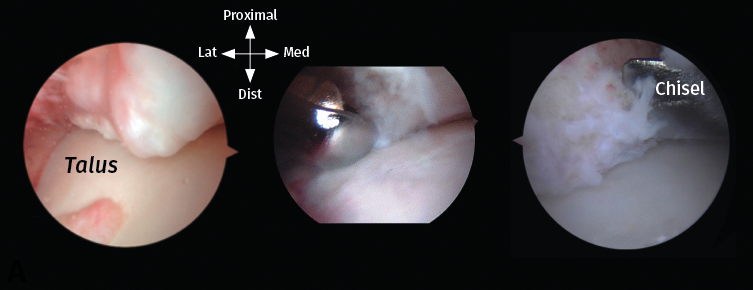

Se reseca en primer lugar el tejido sinovial con un terminal motorizado sinoviotomo del mayor diámetro disponible y con su abertura siempre dirigida hacia el hueso. Los osteofitos se resecan mediante un terminal motorizado de tipo bola de 4 mm (Figura 5). Se facilita la identificación y la resección de estos posicionando el tobillo en flexión dorsal, lo que impide que la cápsula articular anterior los oculte. Además, el astrágalo y su capa articular quedan así protegidos bajo la tibia de posibles daños iatrogénicos. El contorno anterior de la tibia distal se identifica resecando el tejido sinovial que lo cubre; seguidamente, se reseca el osteofito y esta resección se amplía extendiéndola al propio maléolo interno hasta liberar completamente el pinzamiento. La exposición se puede mejorar llevando el tobillo a una posición de flexión dorsal forzada; con esta maniobra se aumenta el área de trabajo del receso capsular anterior.

Figura 5. Descripción del procedimiento quirúrgico paso a paso. A: un osteofito se encuentra a nivel anterior de la tibia distal; B: el tejido sinovial se reseca con un sinoviotomo de ventana grande con la abertura siempre dirigida hacia el hueso; C: los osteofitos se escinden con un sinoviotomo o fresa artroscópica de 4 mm, o  con un pequeño escoplo.